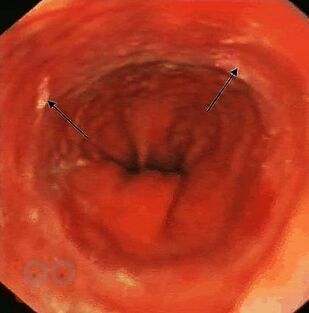

Хирургическое лечение язвенной болезни в настоящее время осуществляется преимущественно операцией резекции желудка. После резекции желудка по методу Бильрот-II 12-перстная кишка с ее богатыми рефлексогенными и гормональными зонами оказывается выключенной из пассажа пищи. Болезни оперированного желудка, как сравнительно новый раздел брюшной хирургии, в систематизированном и более или менее полном изложении в научной литературе практически не представлен. В руководствах по оперативной хирургии и хирургическим болезням об этом говорится вскользь. В периодической печати имеется разрозненный материал, в котором авторы излагают свои личные наблюдения по какому-то одному вопросу этой большой и сложной проблемы. Коллектив кафедры и клиники госпитальной хирургии им. А.Г. Савиных имеет богатый, более 90 лет, опыт диагностики и лечения пациентов с заболеваниями желудка и 12-перстной кишки, который представлен в данном издании иллюстрированном авторскими рисунками.